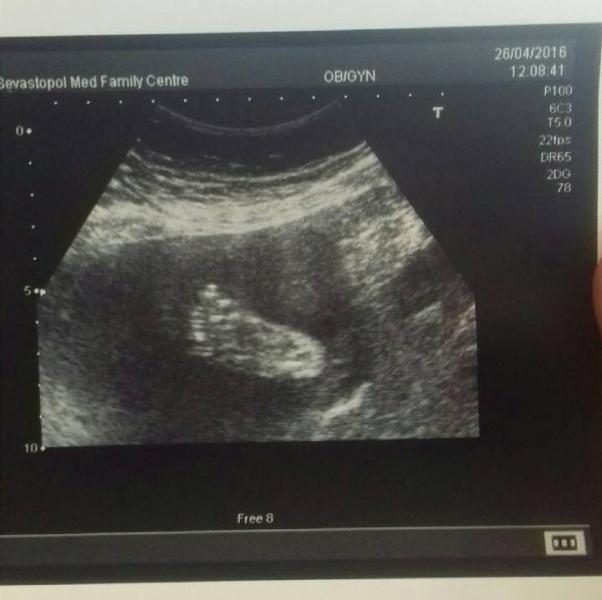

Были мы на узи) 25 неделек, все хорошо) и у нас есть первые два фото, Сюда выложу одно))))